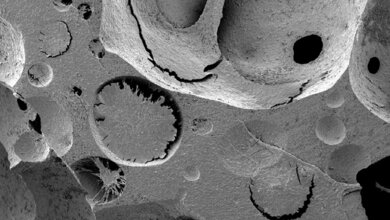

3.605 Patienten/-innen konnte die DGFG 2019 mit einem Hornhauttransplantat versorgen. Im Durchschnitt werden pro Jahr rund 7.000 Hornhauttransplantationen in Deutschland durchgeführt. „Mehr als jede zweite Hornhaut kommt von der DGFG. Wir können mittlerweile bei der Hornhauttransplantation die meisten Anfragen innerhalb weniger Wochen erfüllen“, sagt Börgel. Unter den vermittelten Hornhäuten waren 383 Hornhautlamellen (LaMEK) für die DMEK-Operation (Descemet Membrane Endothelial Keratoplasty). Hier ersetzen Ärzte nur eine dünne Schicht der Hornhaut, wodurch sich die Sehfähigkeit der Patienten deutlich schneller erholt und das Infektionsrisiko minimal bleibt.

Mithilfe von Spendengeldern konnte die DGFG 2019 eine Fotowanderausstellung initiieren, die mittlerweile in allen fünf Gesellschafterkliniken der DGFG zu sehen ist. Fotografin Alexandra Bidian begleitete für die Reportage „Wieder-Sehen“ eine Patientin mit Fuchs‘scher Endotheldystrophie auf ihrem Weg vom trüben Blick zurück zum klaren Sehen. Die Motive der Reportage zeigen, wo das Spendergewebe herkommt, wie es aufbereitet und gelagert wird und welche Schritte außerdem bis zur erfolgreichen Transplantation notwendig sind.